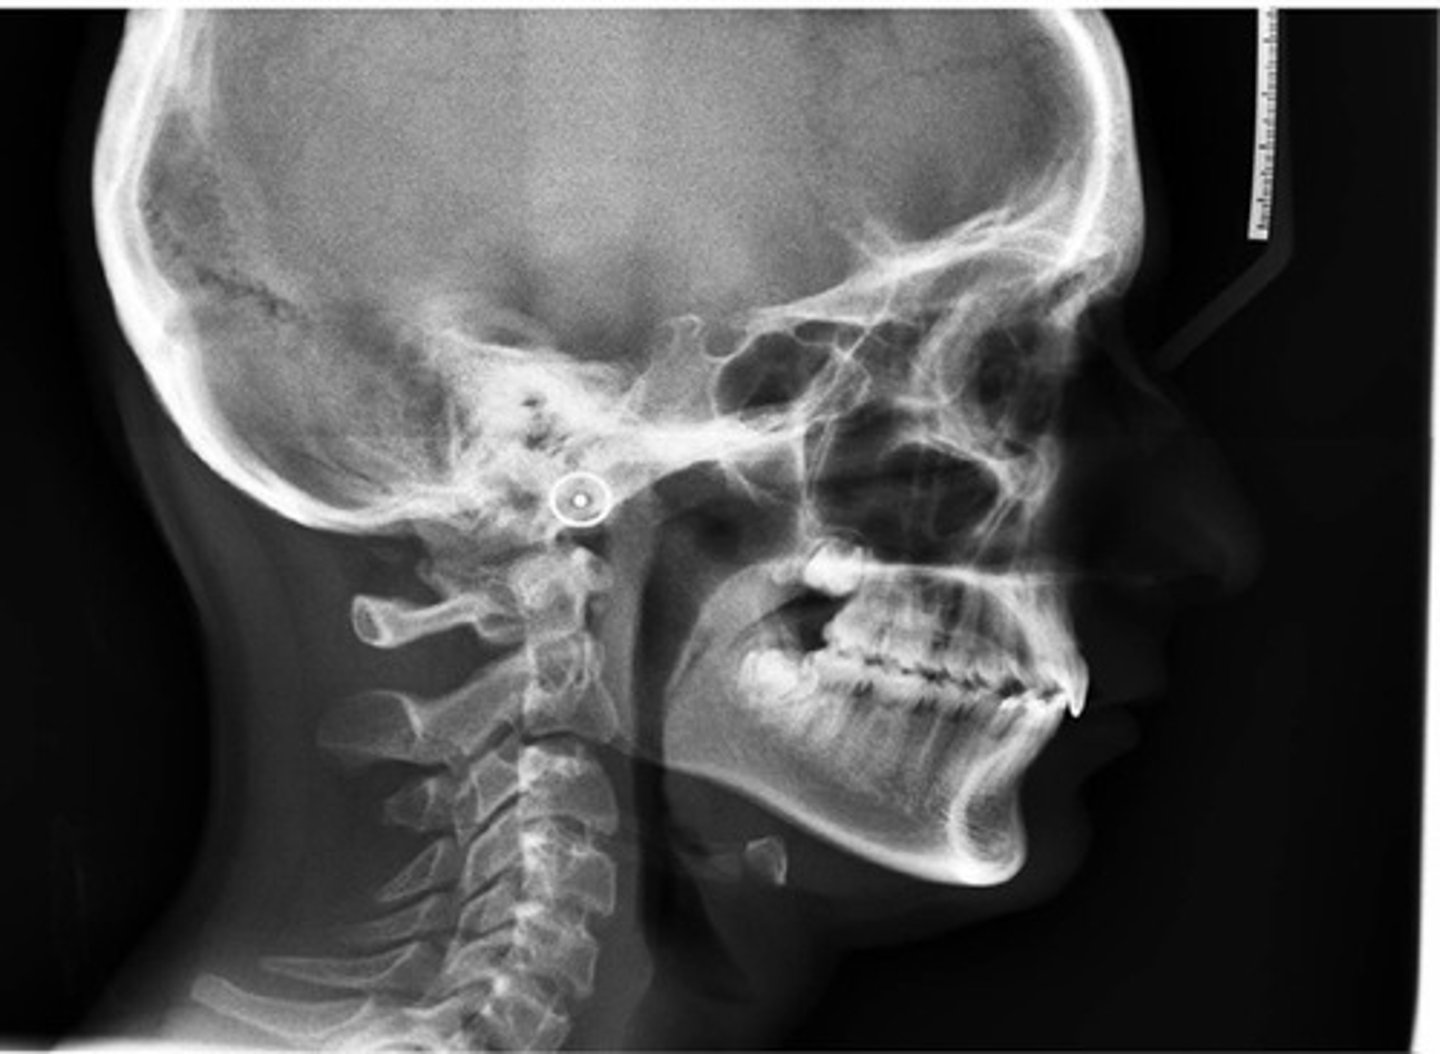

Cephalometric radiograph

extraoral radiograph of the bones & tissues of the head

Cephalometric radiograph purpose

enables the dentist to capture a complete radiographic image of the side of the face